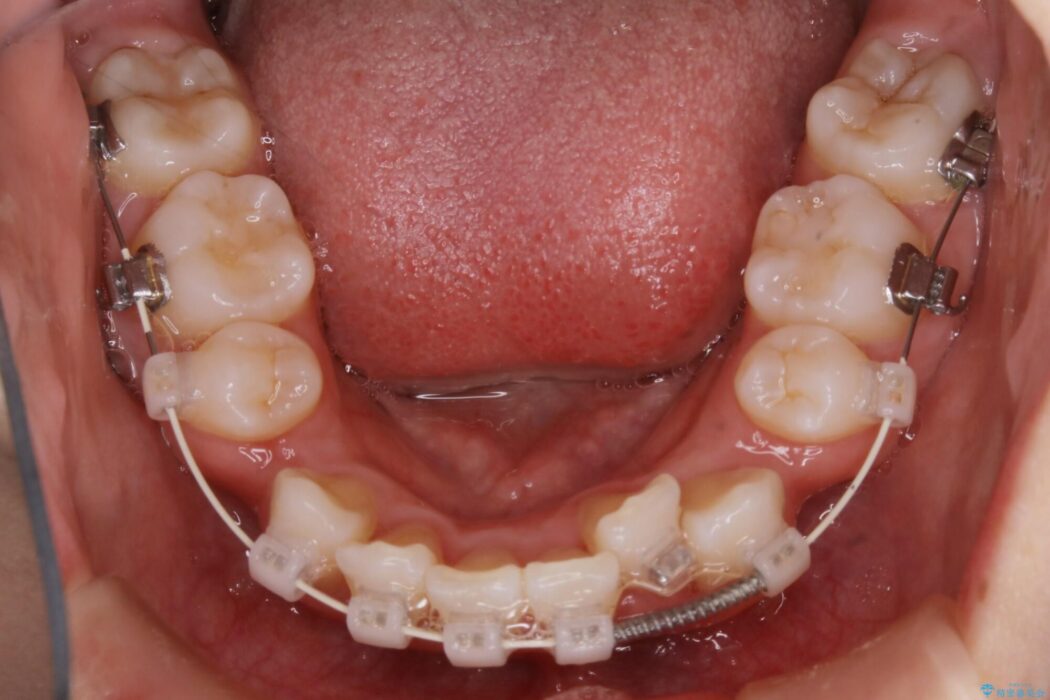

治療概要

- 患者様:20代女性

- 治療期間:2年3ヶ月

- 矯正装置:ワイヤー(審美装置)

- 概算治療費:107.8万円

※費用は治療当時の料金となります - 担当医:福本健生

検査したところ歯に対して骨が上顎・下顎共に小さいことがわかりました。

それによりスペースが少なく歯列がガタついたり前方傾斜する生え方となっていました。

よって本症例では抜歯により歯の本数を減らすことにより整えるスペースを確保してワイヤー装置にて歯列矯正を行うこととしました。